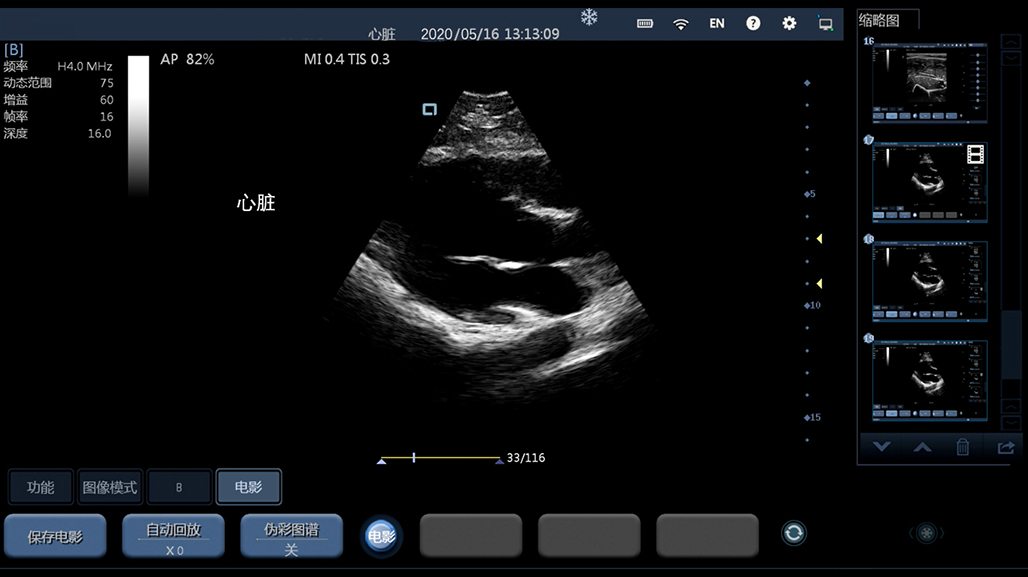

妇科产科

心脏